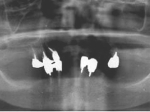

片側2歯欠損片側2歯欠損片側2歯欠損 主訴-入れ歯を使ってみたが違和感強くてダメ。固定のものにしたい。術前下顎口腔内(鏡像) 二次オペ時(鏡像)二次オペ時(鏡像)二次オペ時(鏡像) 術後術後術後、左下奥2本インプラント(鏡像) 術後(レントゲン)術後(レントゲン)術後(レントゲン)、左下奥2本インプラント

両側5歯症例

両側5歯症例両側5歯症例両側5歯症例 主訴-義歯のバネが壊れて手前の歯が痛んできた。 術前(旧義歯装着、鏡像) 術前(下顎粘膜面、鏡像)術前(下顎粘膜面、鏡像)術前(下顎粘膜面、鏡像) 術前レントゲン術前レントゲン術前レントゲン 術前口腔内(正面観)術前口腔内(正面観)術前口腔内(正面観)

術後(鏡像)術後(鏡像)術後(鏡像) 術後口腔内(正面観)術後口腔内(正面観)術後口腔内(正面観)もう入れ歯は要らなくなりました。 術後レントゲン術後レントゲン術後レントゲン